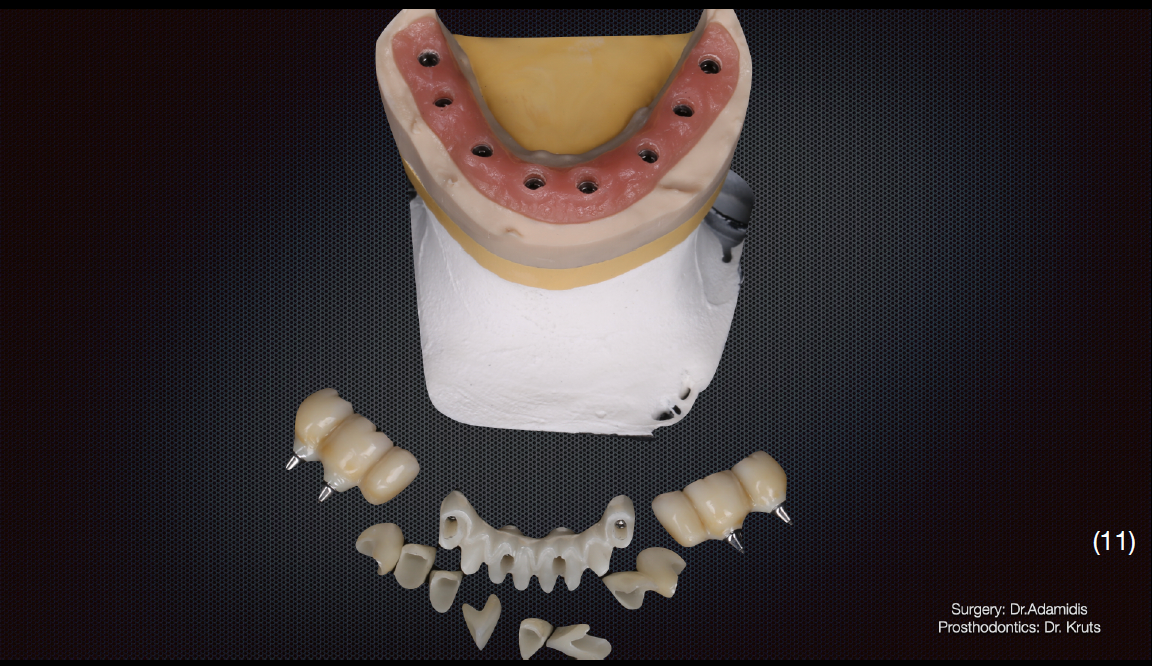

На нижню щелепу було виготовлено роздільну конструкцію. В бічних ділянках – мостоподібні протези на гвинтовій фіксації з рівня імплантату.

У фронтальній ділянці комбінована конструкція – каркас із діоксиду цирконію, фіксований до імплантатів гвинтами, на який цементуються коронки із прес-кераміки. Такий тип конструкції вибрано через високу надійність та прогнозованість в довготривалій перспективі, що підтверджується даними клінічних досліджень, а також легкість в обслуговуванні.